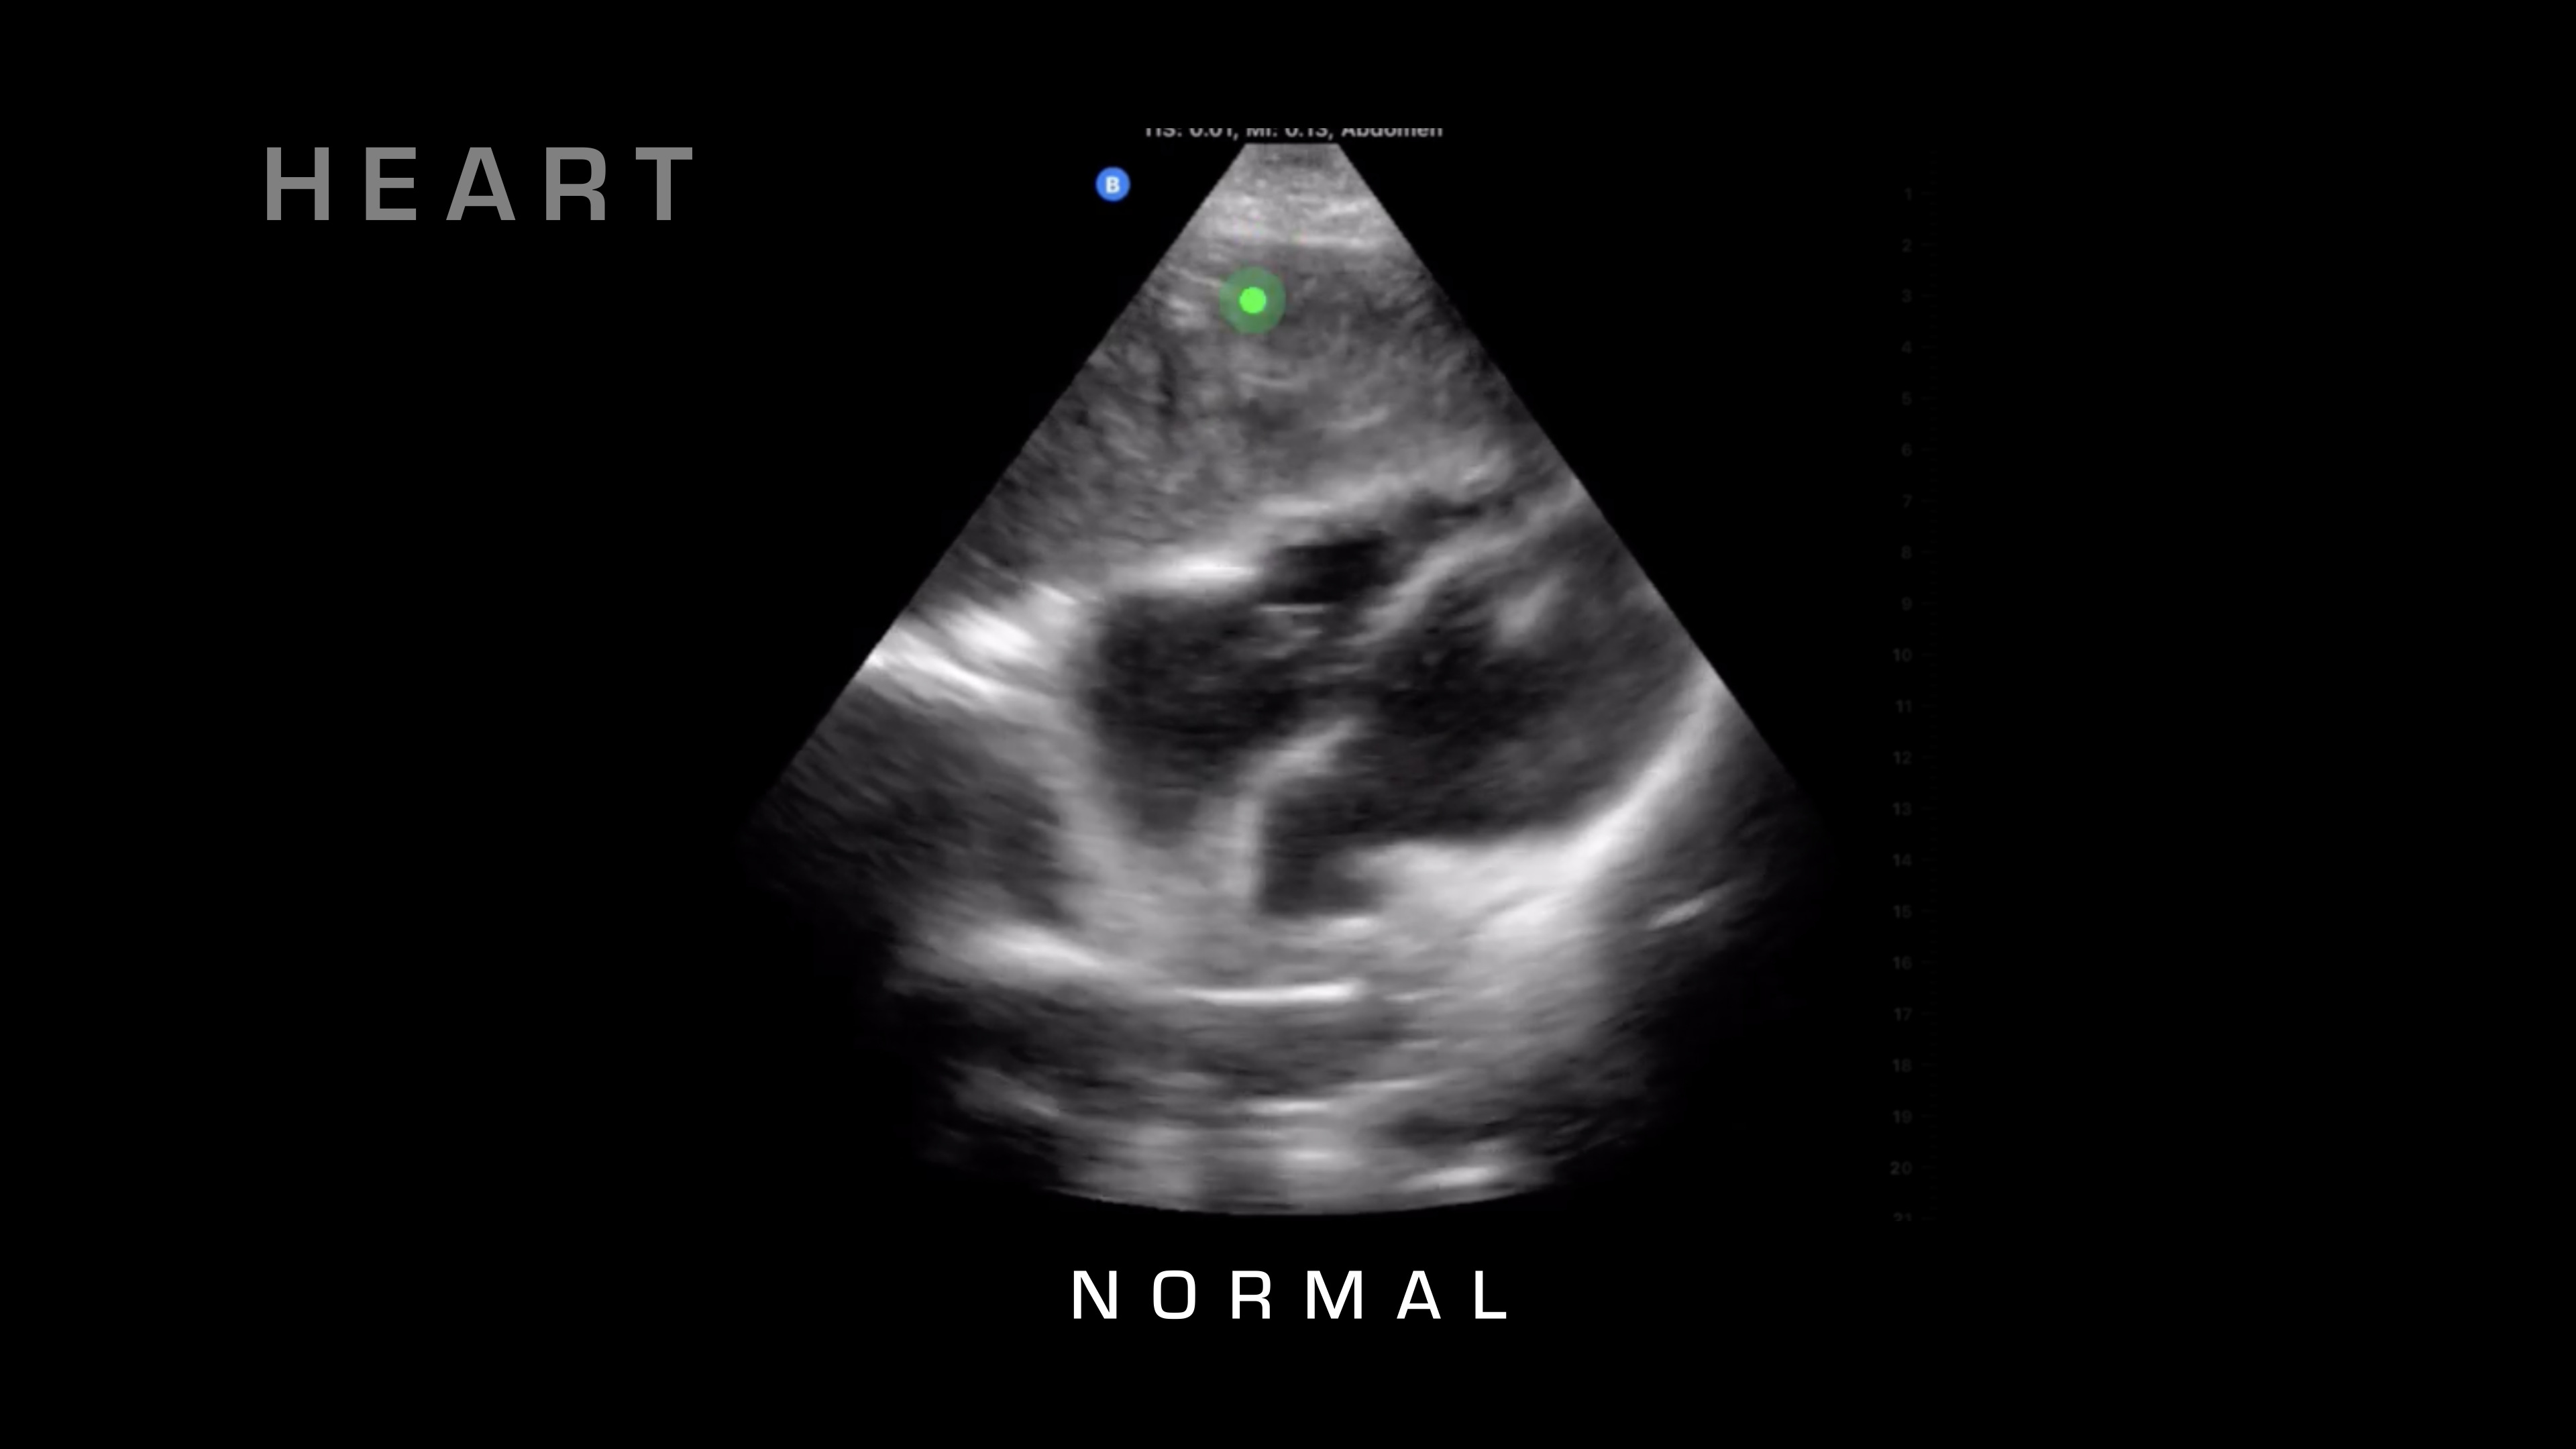

So next up on our FAST exam, what we're going to do is we're going to take a look for cardiac tamponade, and we can also get a nice view of cardiac activity. So for cardiac tamponade, what I'm looking at is the heart beating. I'm looking for that sac surrounding the heart, and then if there's fluid in between those two, typically there shouldn't be any fluid between those two, but in cardiac tamponade, fluid will go in there, blood will go into that cavity, and it'll build up and build up, then restricting the heart and reducing cardiac output.